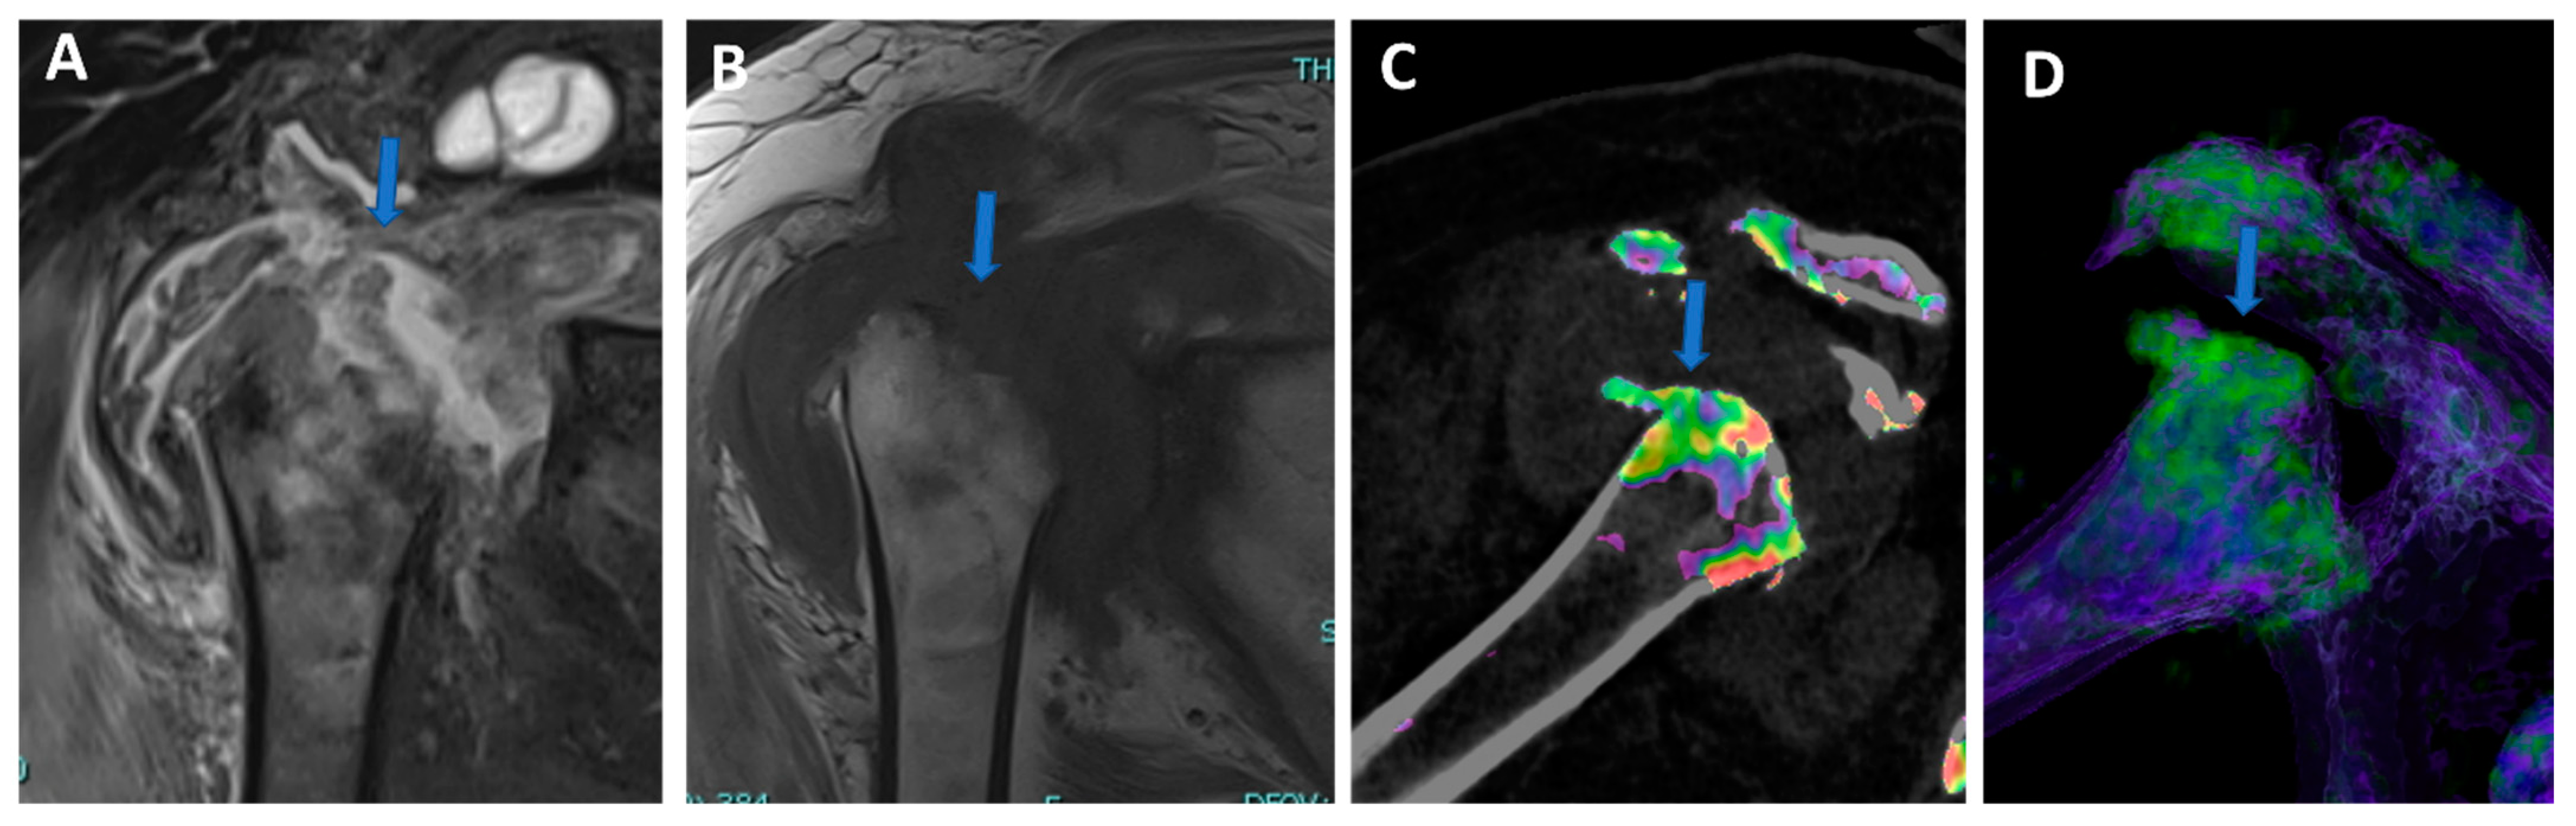

Figure 1.

Recurrent anterior shoulder dislocation in a previously operated patient. By using multiple applications, DECTA can help in the diagnosis of anterior shoulder dislocation, potentially representing a “one-stop one-shop” procedure. A blended virtual 120 kVp axial CTA image (A) shows anterior labral and glenoid rim disruption (arrow). A VNC image on the axial (B) and sagittal (E) planes helps in the evaluation of bone morphology, allowing correct glenoid surface measurement (arrow). In the axial iodine map (C), it is possible to better evaluate the morphology of the anterior labrum (arrow). In the axial BME 2D superimposed image (D), it is possible to recognize edema of the anterior glenoid rim (blue arrow) and subtle edema of the posterior aspect of the humeral head (white arrow), which is consistent with recent recurrent dislocation.